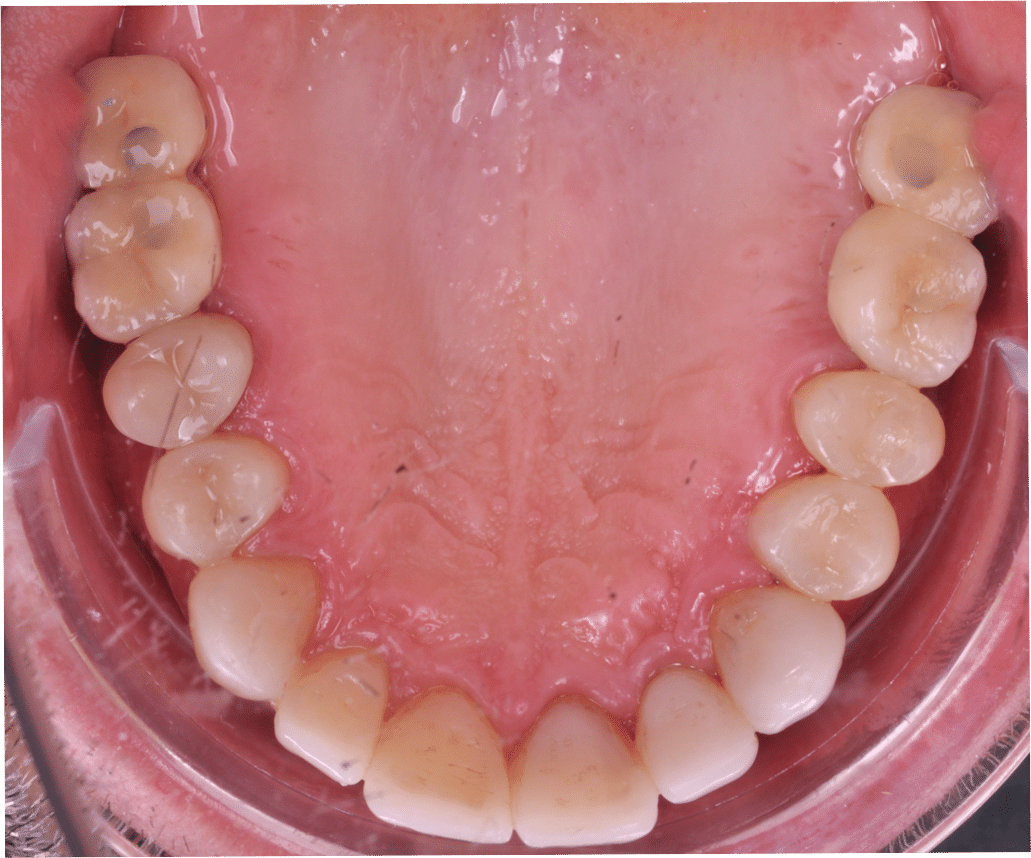

Împreună cu pacientul, am optat pentru inserarea implantelor cu ajutorul ghidului chirurgical pentru a plasa implantul în poziția protetică ideală și pentru a permite realizarea coroanelor insurubate pe implant. A fost efectuată scanarea digitală a arcadelor și a ocluziei pacientului, iar împreună cu tehnicianul radiolog de la DigiRay a fost suprapus fișierul .stl al amprentei digitale peste fișierul .dcm de la CBCT, utilizând software-ul 3Shape.

S-a planificat individual poziția și axul de inserție al fiecărui implant.